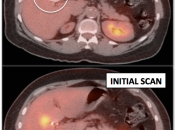

- Assess Response to Therapy

Post-Operative Inflammatory Changes

Post-surgical inflammatory changes can present a diagnostic challenge for the PET/CT radiologist.

Very commonly, surgery results in ill-defined inflammatory soft tissue density in the operative bed, which can be difficult to distinguish from residual or recurrent malignancy. Further complicating matters, this post-operative inflammatory soft tissue is often intensely FDG-avid.

During the first weeks following surgery, distinguishing this ill-defined hypermetabolic inflammatory soft tissue from residual or recurrent malignancy can be exceedingly difficult. Frequently, only a follow up exam will permit this distinction:

Increased Suspicion for Malignancy:

- Soft tissue is intensely avid > 2 months after surgery (> 3-months after radiation). Exception: inguinal herniorrhaphy (discussed here).

- Hypermetabolic activity is limited to only a very focal portion of the soft tissue density in the operative bed.

- Any increase in size and/or metabolic activity of the soft tissue on a follow-up exam.

- Evidence of co-existing active malignancy exists (e.g. adjacent hypermetabolic nodes).